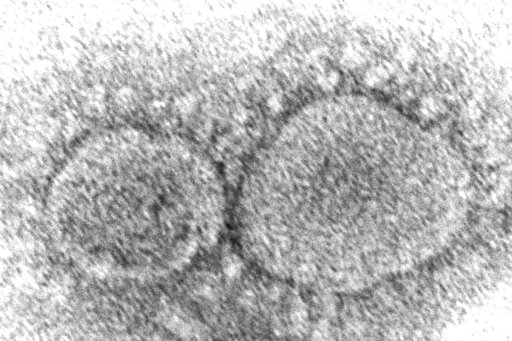

The coronavirus mutant that is now dominant in the United States is a member of the omicron family but scientists say it spreads faster than its omicron predecessors, is adept at escaping immunity and might possibly cause more serious disease.